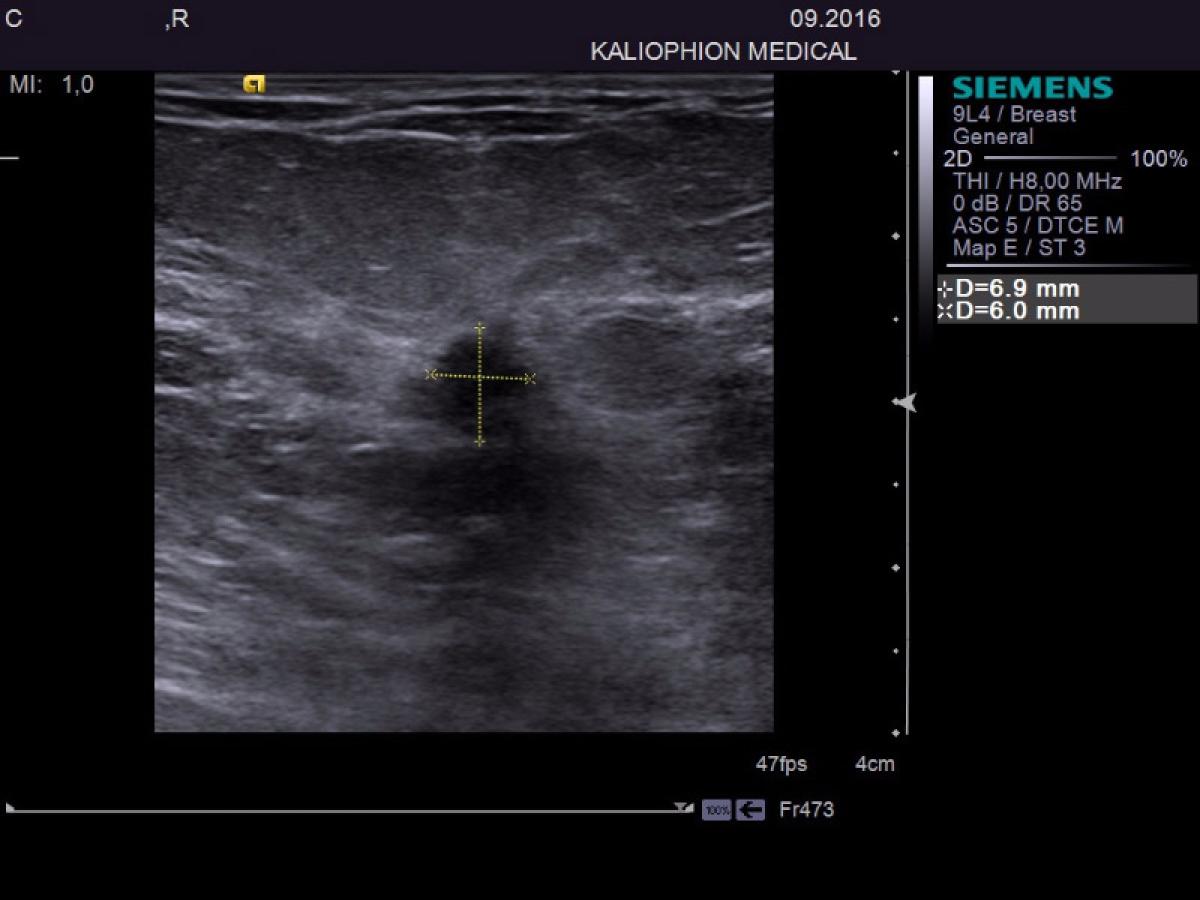

• din nou o brăileancă a ieşit învingătoare în lupta cu cancerul de sân • dr. Claudiu Leonida i-a descoperit la sânul drept o tumoră de 6,9 mm, ce părea a fi malignă • acesta i-a recomandat femeii să facă investigaţii suplimentare şi să o extirpe • ajunsă la Bucureşti, doctorii i-au confirmat temerile dr. Leonida, iar pacienta a intrat în operaţie • cazul a fost unul fericit, cancerul fiind descoperit în fază incipientă

Brăileanca ne-a povestit că a fost tot timpul atentă cu starea sa de sănătate şi, periodic, mergea la controale medicale. Aflând de cabinetul “Kaliophion Medical” şi de dr. Claudiu Leonida, s-a programat la un control de rutină, fapt care putem spune că i-a salvat viaţa. “Am ajuns la clinică la ora stabilită şi, după ce mi-a adresat câteva întrebări referitoare la istoricul meu medical, am început ecografia. După efectuarea ambelor etape de ecografie, domnul doctor mi-a spus că în sânul drept se observă o tumoră cât un bob de mazăre, de doar 6,9 milimetri, pe care o suspectează că este malignă, având în vedere aspectul imaginilor ecografice şi că trebuie urgent investigată suplimentar, apoi extirpată, datorită faptului că are o dimensiune foarte mică”, a povestit pacienta.